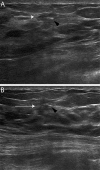

Lymphoepithelioma-like carcinoma of the breast is a rare malignancy, with fewer than 20 cases documented in the literature. Given the paucity of reported cases, there is limited information available to guide the diagnosis and management of patients with this tumor. We present a case of a 39-year-old woman with a palpable right breast mass that was initially diagnosed by core needle biopsy as infiltrating carcinoma with prominent lymphoplasmacytic stroma. Subsequent neoadjuvant chemotherapy with docetaxel, doxorubicin, and cyclophosphamide resulted in a marked decrease in the size of the mass. After wide local surgical excision, pathology revealed a lymphoepithelioma-like carcinoma of the breast. Given the excellent treatment response, our experience may help clinicians determine future therapeutic strategies for this rare breast tumor.